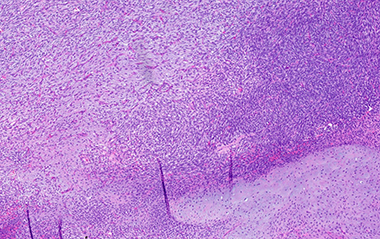

B. Complex cystic architecture (low power)

Pheochromocytoma was identified comprising 50% of tumor volume. In addition, the lesion contained a primitive round cell component possibly neuroblastoma with focal neuroblastic differentiation (20%) and a malignant peripheral nerve sheath tumor (30%) with heterologous elements (cartilage). Areas of hemorrhage and necrosis were noted resulting in cystic degeneration.

Microscopically, transition between the tumors may be blended or abrupt, pheochromocytoma is almost mostly the predominant pattern with apparent zellballen or variant patterns, GN contains ganglion cells in background of Schwann cells, GNB will have immature and maturing neurons, neuropil and Schwann cells, NB will have small round blue cells and MPNST will show malignant spindle cells with high mitotic count. Note that to designate as composite, although there is no precise portion of the components specified as a definition, there must be complete tumor patterns and not just scattered neurons. Overall, patterns of growth, intermixed cellular components, and immunohistochemistry usually allow this tumors separation from its differential diagnoses.